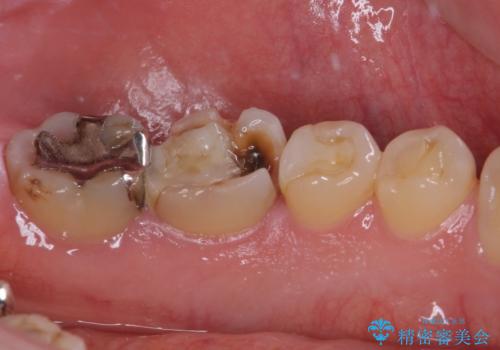

奥歯は虫歯が放置されていましたが、特に症状はなく歯髄の状態も正常でした。

前歯、奥歯ともにオールセラミッククラウンやセラミックインレーにて治療を行うこととしました。